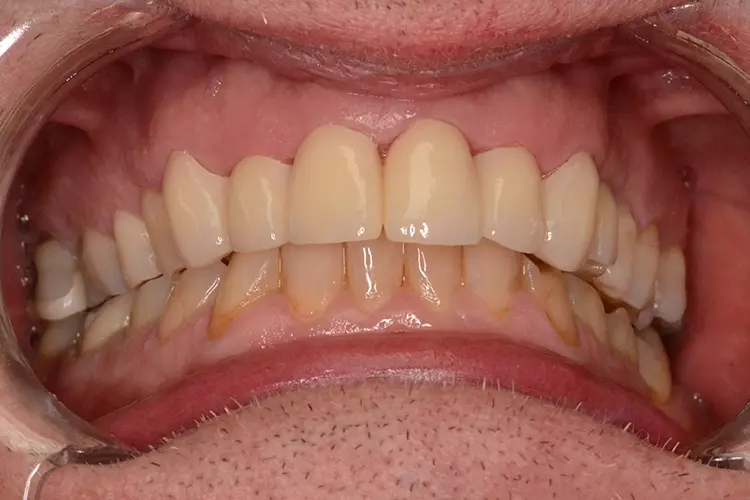

Bei dem heute 49-jährigen Patienten wurde seit Kindertagen versäumt, die Ober- und Unterkieferzahnbögen kieferorthopädisch auszurichten. Der Patient leidet seitdem stark unter seinen Zahnfehlstellungen.

Die Fraktur des stark elongierten Zahnes 21 war für den Patienten der Ausgangspunkt, sowohl die Front des Ober- als auch des Unterkiefers prothetisch überarbeiten zu lassen. Dabei wurde der frakturierte Zahn 21 durch ein navigiert eingesetztes Sofortimplantat ersetzt, während die verschachtelt stehenden Zähne 12 und 42 durch eine Brückenversorgung korrigiert wurden (Abb. 4a-j).